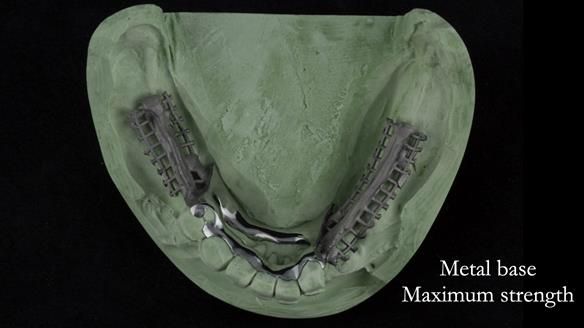

Instead, we made a Scandinavian-style, metal-based lower RPD.

It was made promptly, then relined gradually over the following year

to optimise fit, comfort, and support.

It’s worth saying that the lower denture in this case was made in the early days of Rowan and me using the Scandinavian approach. Rowan cast the metalwork himself for this denture.

Looking back, we would make this denture more hygienic now. The design and finish would be more refined and delicate, particularly when compared with the upper metalwork, which was made later using Chris Hesketh’s chrome work. I will discuss this in detail at the study club.

That said, the lower denture worked beautifully. It did exactly what it was meant to do, even though, by today’s standards, it looks a little agricultural.

Scandinavian metal-based RPDs:

- support compromised teeth

- reduce the risk of fracture

- allow predictable addition of teeth

- help mobile teeth survive longer